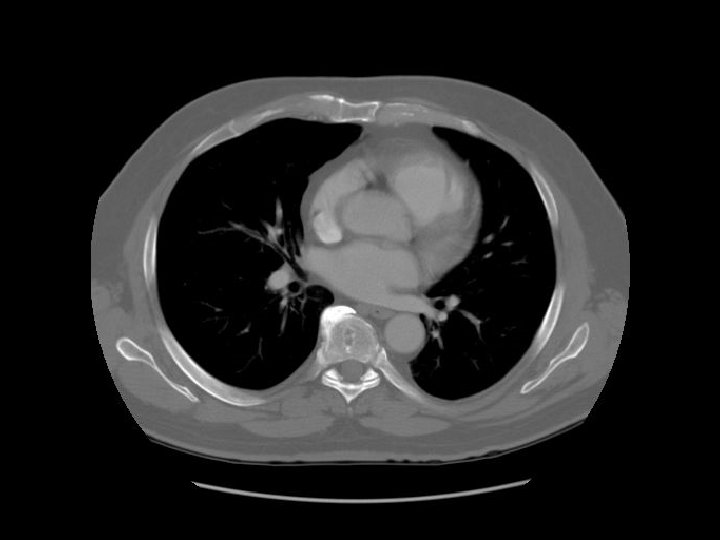

Ascending aorta Main pulmonary artery Descending aorta

Contrast in SVC is diluted by blood from the azygous vein. Esophagus Azygous vein

Left pulmonary artery Carina

Right pulmonary artery Main pulmonary artery RUL bronchus Left pulmonary artery

Left main bronchus

SVC Intermediate bronchus LUL division

Ascending aorta

Rt atrium

Pulmonary vein Lt atrium

A: Aortic root RV RA A LV LA

Aortic valve

Rt ventricle Lt ventricle

Interventricular septum